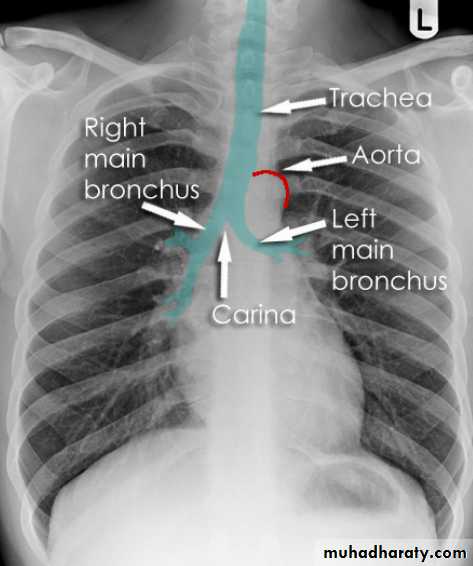

Chest imagingHilar structuresThe hila (lung roots) are complicated structures mainly consisting of the major bronchi and the pulmonary veins and arteries. These structures pass through the narrow hila on each side and then branch as they widen out into the lungs. The hila are not symmetrical but contain the same basic structures on each side.

Each hilum contains major bronchi and pulmonary vessels

There are also lymph nodes on each side(not visible unless abnormal)

The left hilum is often higher than the right

Both hila should be of similar size and density. If either hilum is bigger and more dense, this is a good indication that there is an abnormality.

Lung markings reflects pulmonary vasculature